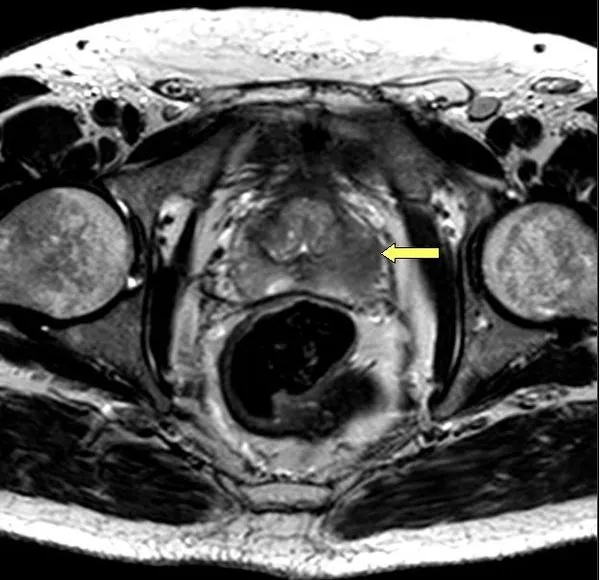

Podczas rezonansu magnetycznego prostaty pacjent przechodzi przez kilka etapów, które są kluczowe dla uzyskania dokładnych wyników. Na początku, przed samym badaniem, personel medyczny wprowadza pacjenta w procedurę, wyjaśniając, co będzie się działo. Następnie pacjent jest proszony o położenie się na stole skanera MRI, a technik ustawia odpowiednio urządzenie, aby uzyskać najlepsze obrazy. W przypadku badania z kontrastem, w tym etapie może być konieczne podanie środka kontrastowego dożylnie, co również wymaga założenia wenflonu.

Podczas samego badania pacjent znajduje się w tunelu skanera, co może być dla niektórych osób nieco nieprzyjemne. Warto wiedzieć, że skanowanie trwa zazwyczaj od 20 do 45 minut. W tym czasie pacjent powinien leżeć nieruchomo, aby uzyskać wyraźne obrazy. Po zakończeniu badania, pacjent może wrócić do normalnych aktywności, a wyniki zostaną omówione podczas kolejnej wizyty u lekarza.